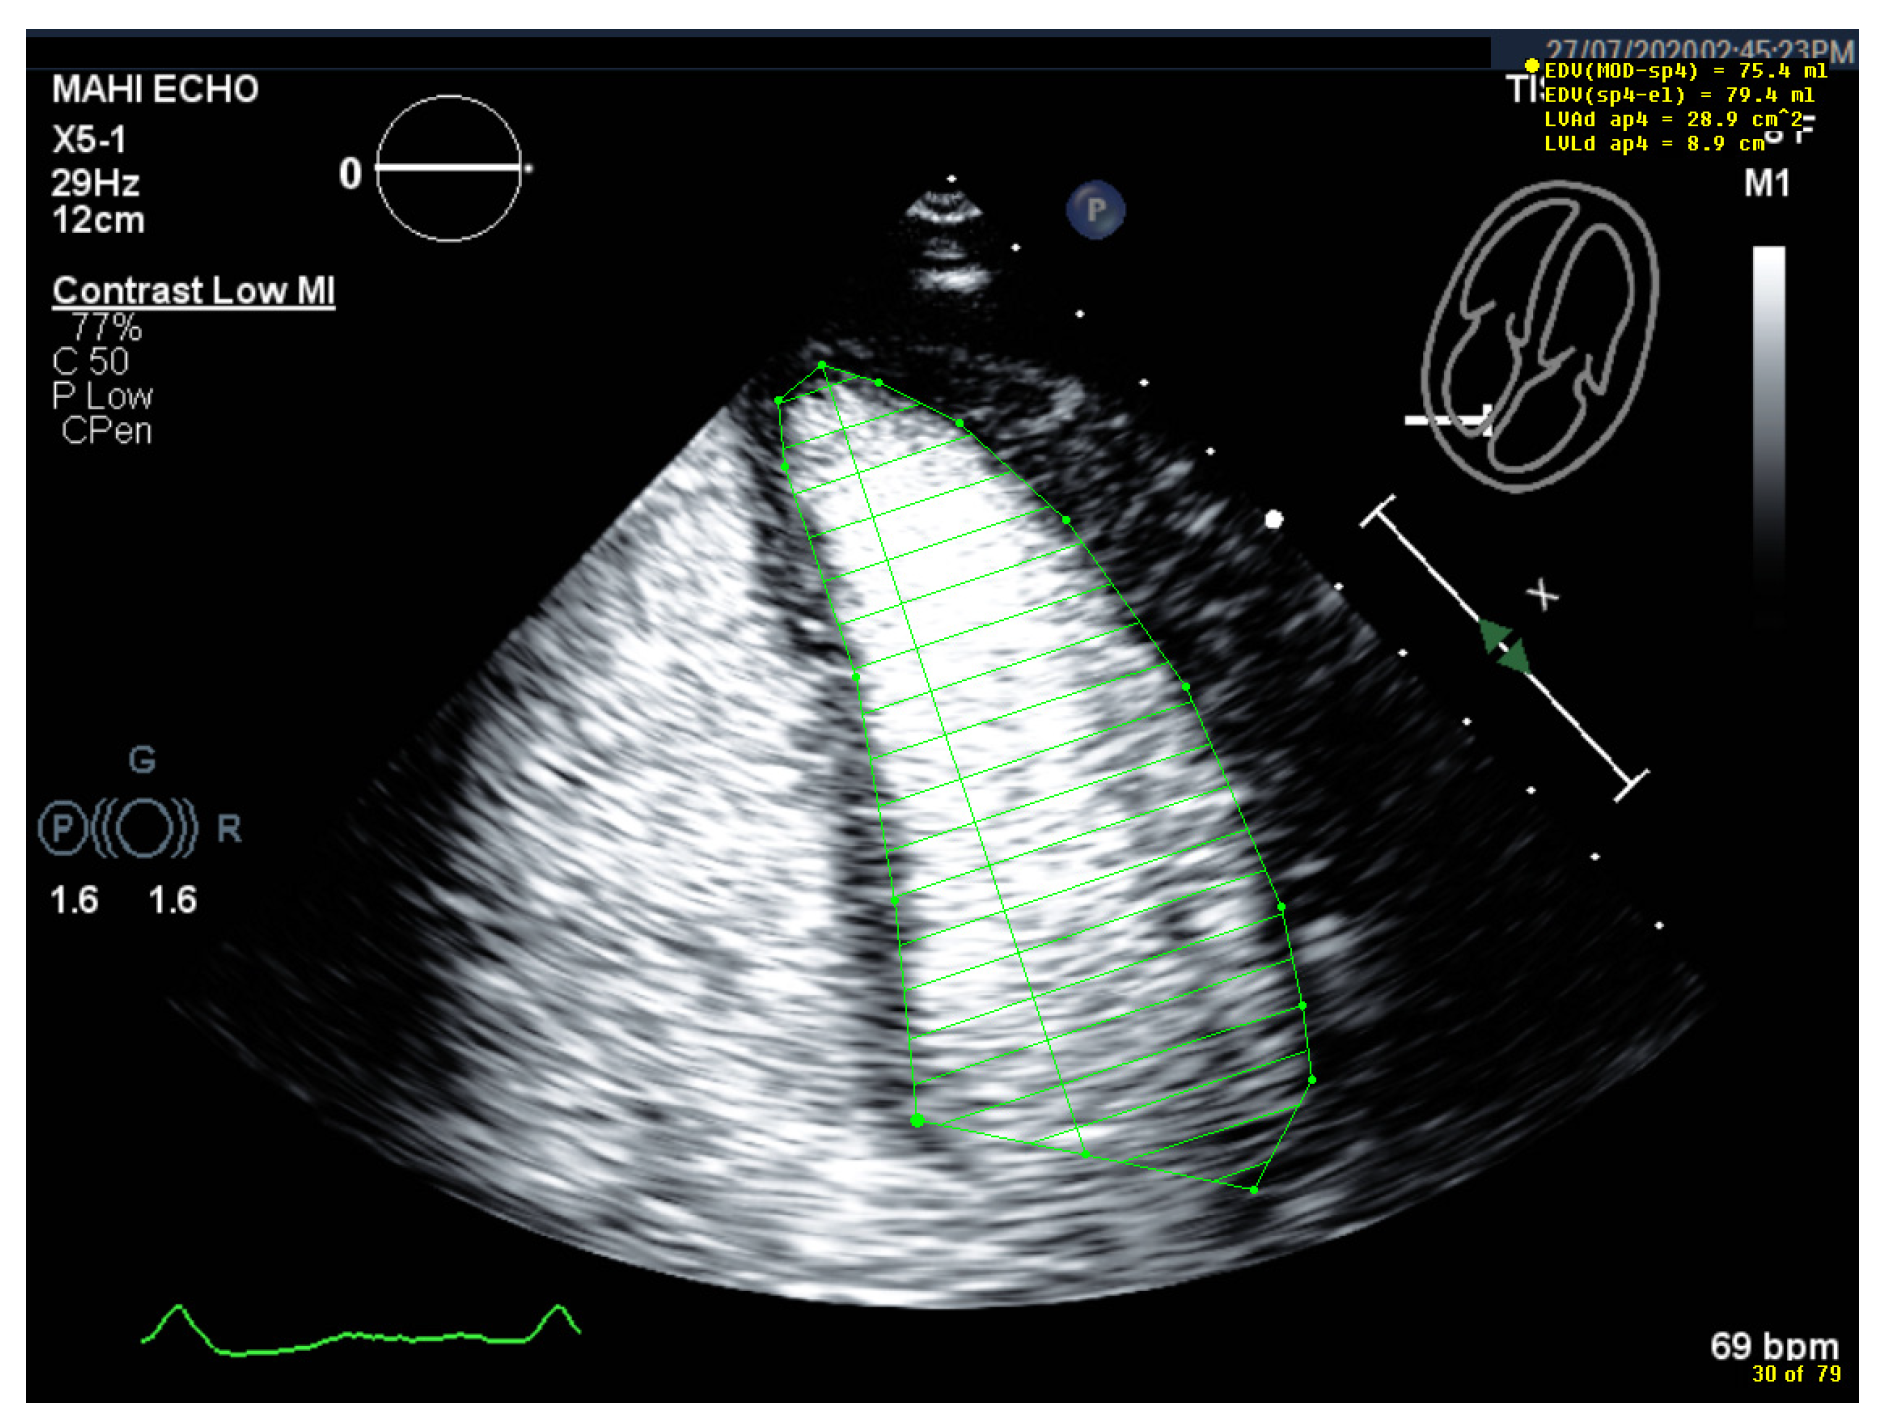

Selection of Foreshortened Loops

Starting Point for the LV Contour at the Mitral Valve Ring Is Incorrect

| 1 | Select unforeshortened loops avoid 4-chamber views, which include anterolateral papillary muscles | When several loops are available, select the one with the longest long axis which impairs tracing of the lateral LV wall |

| 6 | Check the LV length (distance between the middle of the line connecting the mitral ring and the apex) | When the difference in diastolic LV length between 4- and 2-chamber views is <0.5 cm, no major foreshortening can be assumed When the difference is >5 mm, the recording of the view with the shorter LV length is probably not optimal. The other recordings of this view should be reviewed to find the one with the longest LV [59]. |